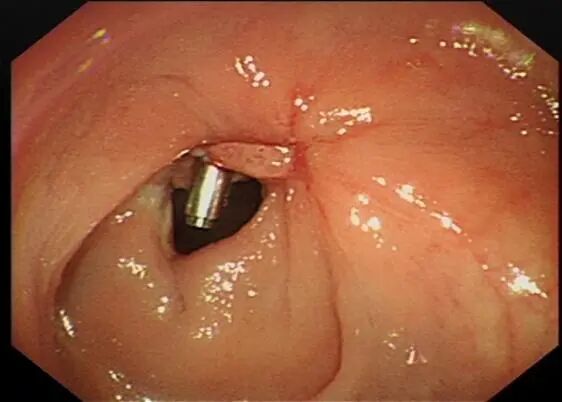

一个月后温大爷返院复查

再次安排了结肠镜检查

可见术口愈合良好

一枚钛夹残留,旁见增生物

圈套器切除后送检

病理回报为炎性息肉,未见癌灶。